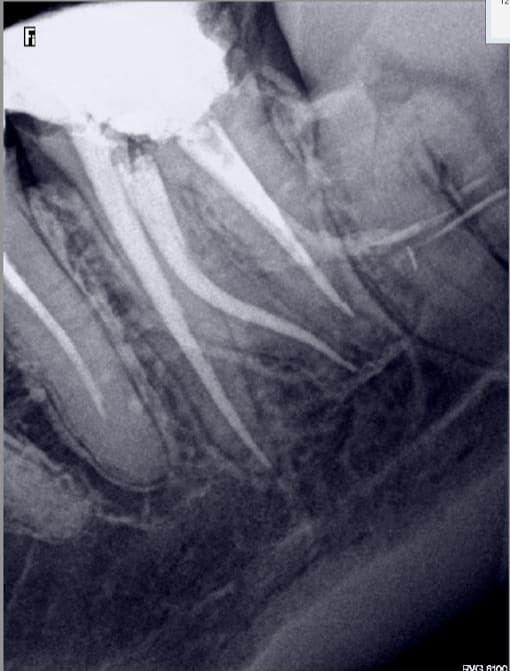

02/02/2017 à 13h20

tu me montres 2 radios en incidence oblique de 2e MV obturés et je m'achète un lab )))

Et d'une. RTE s'il vous plait. -)